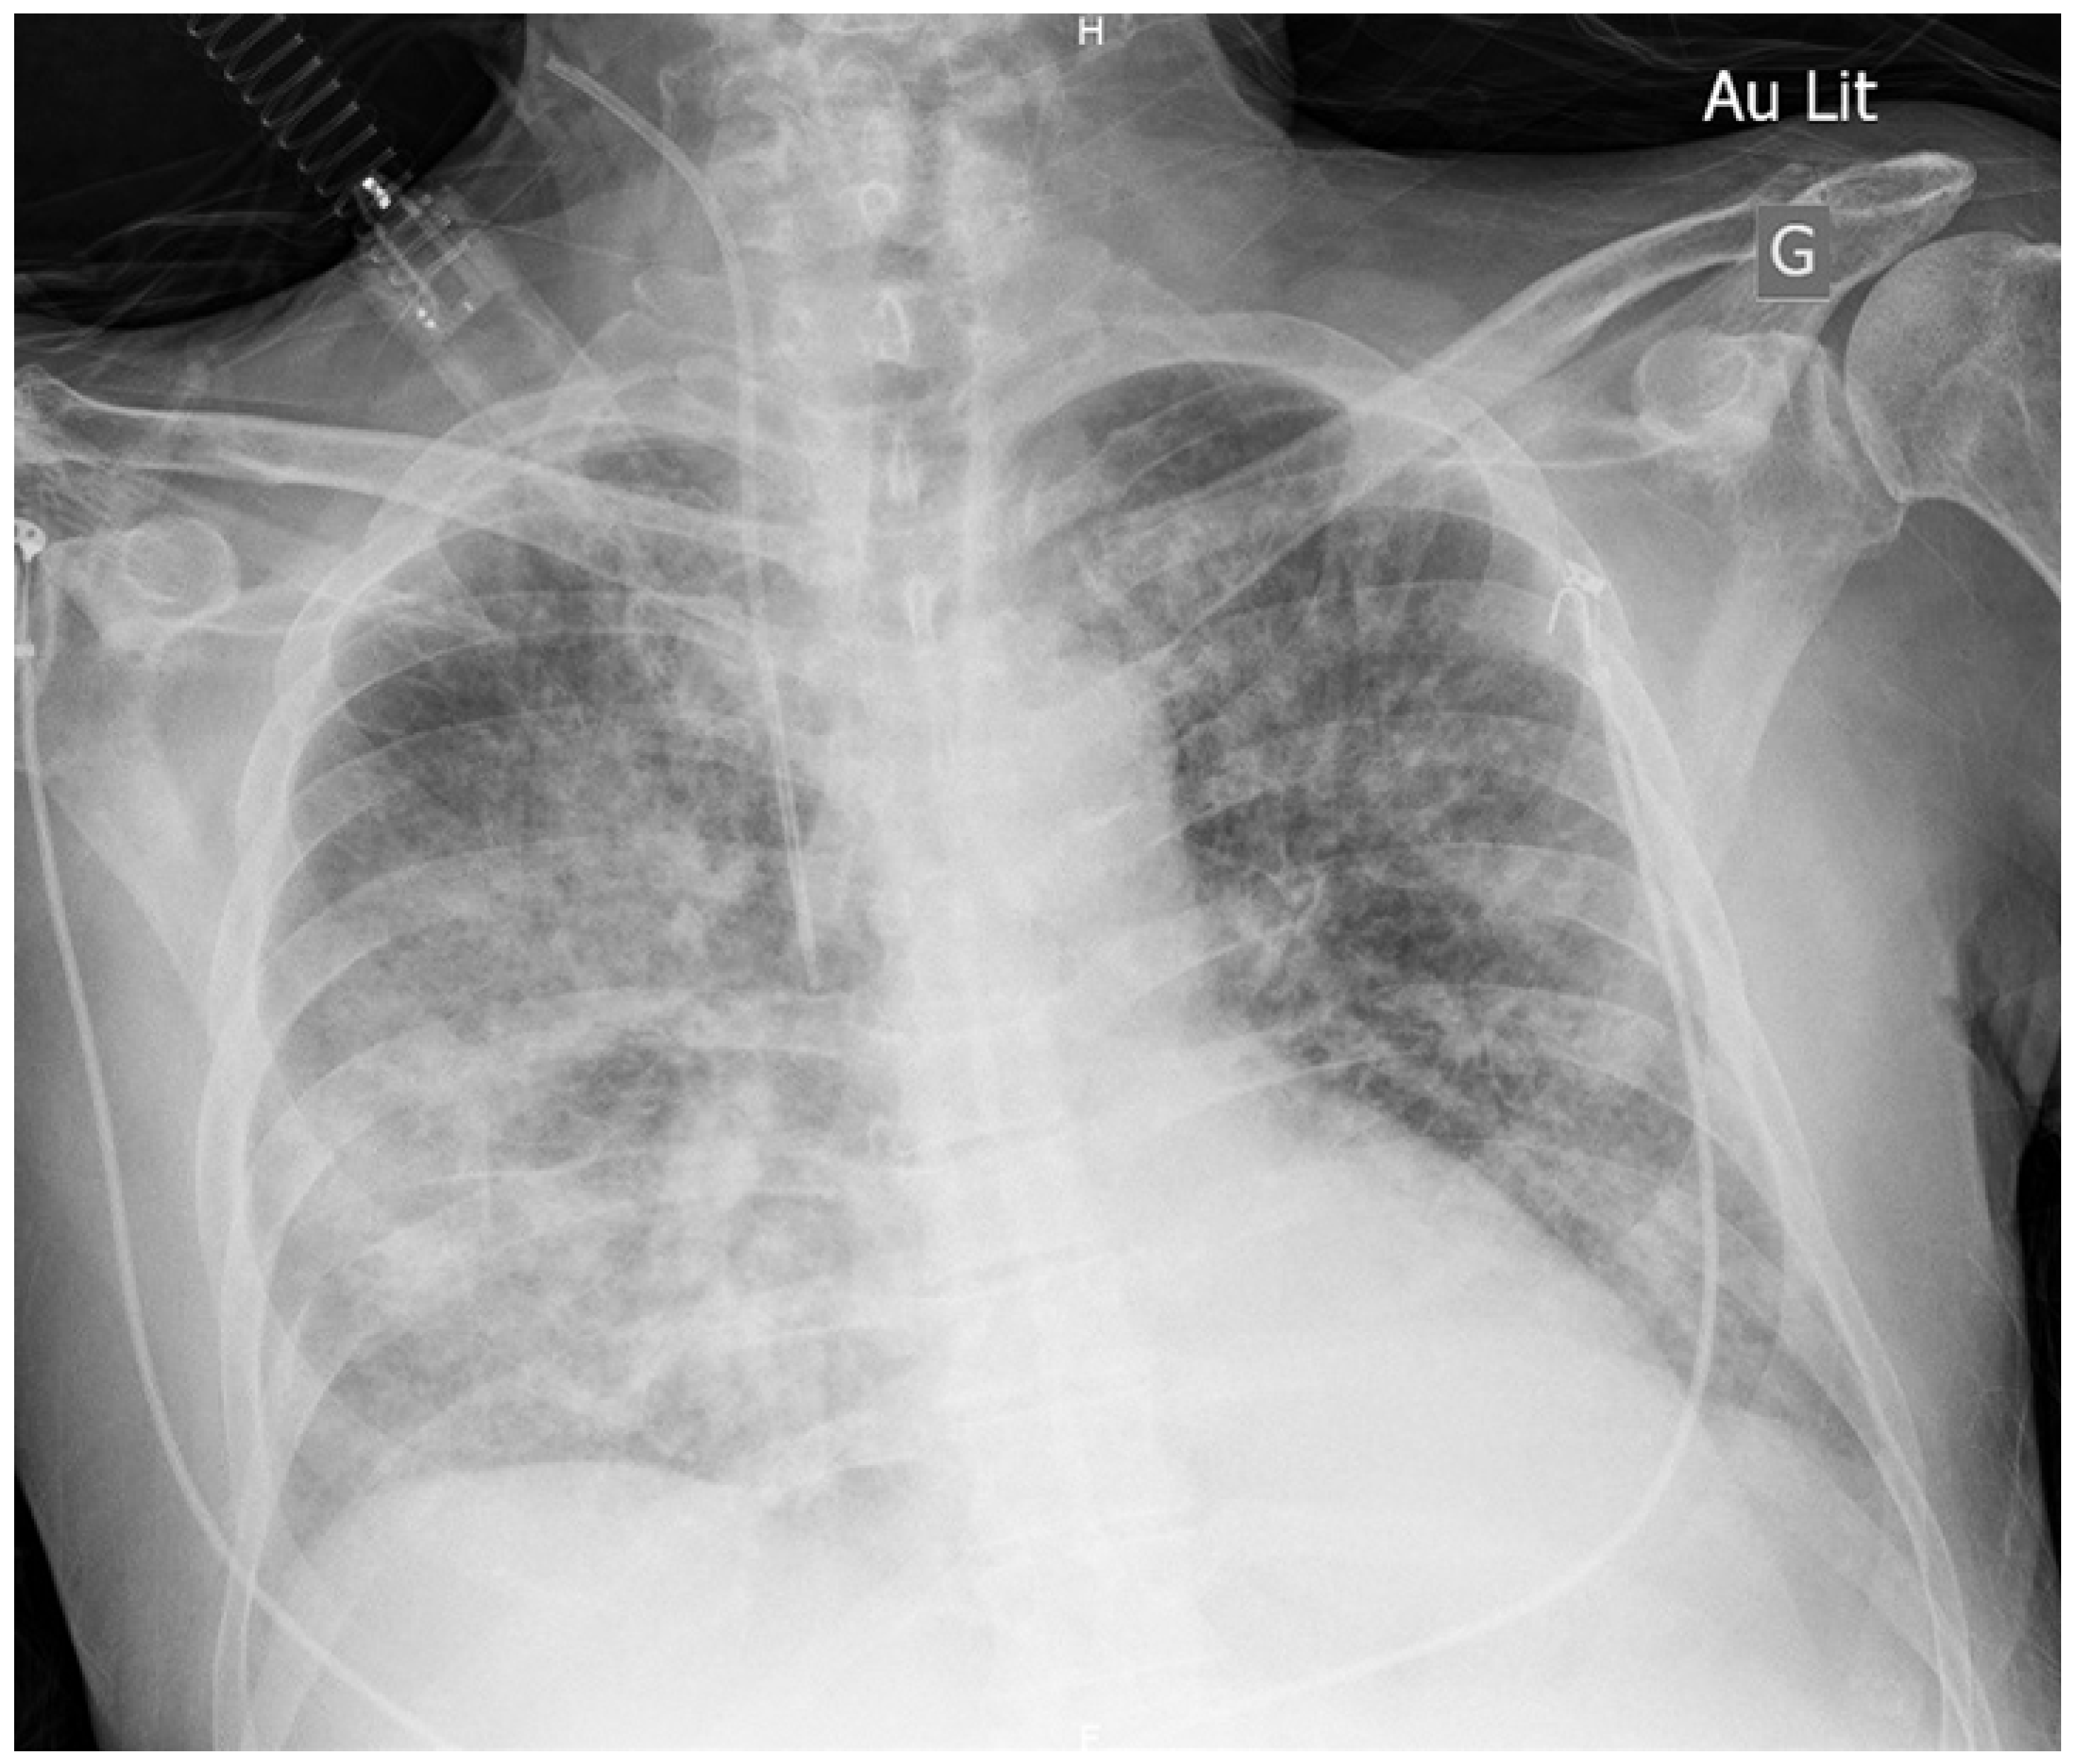

Relapsing Terlipressin-Induced Acute Pulmonary Oedema in a Patient with Hepatorenal Syndrome

Case description